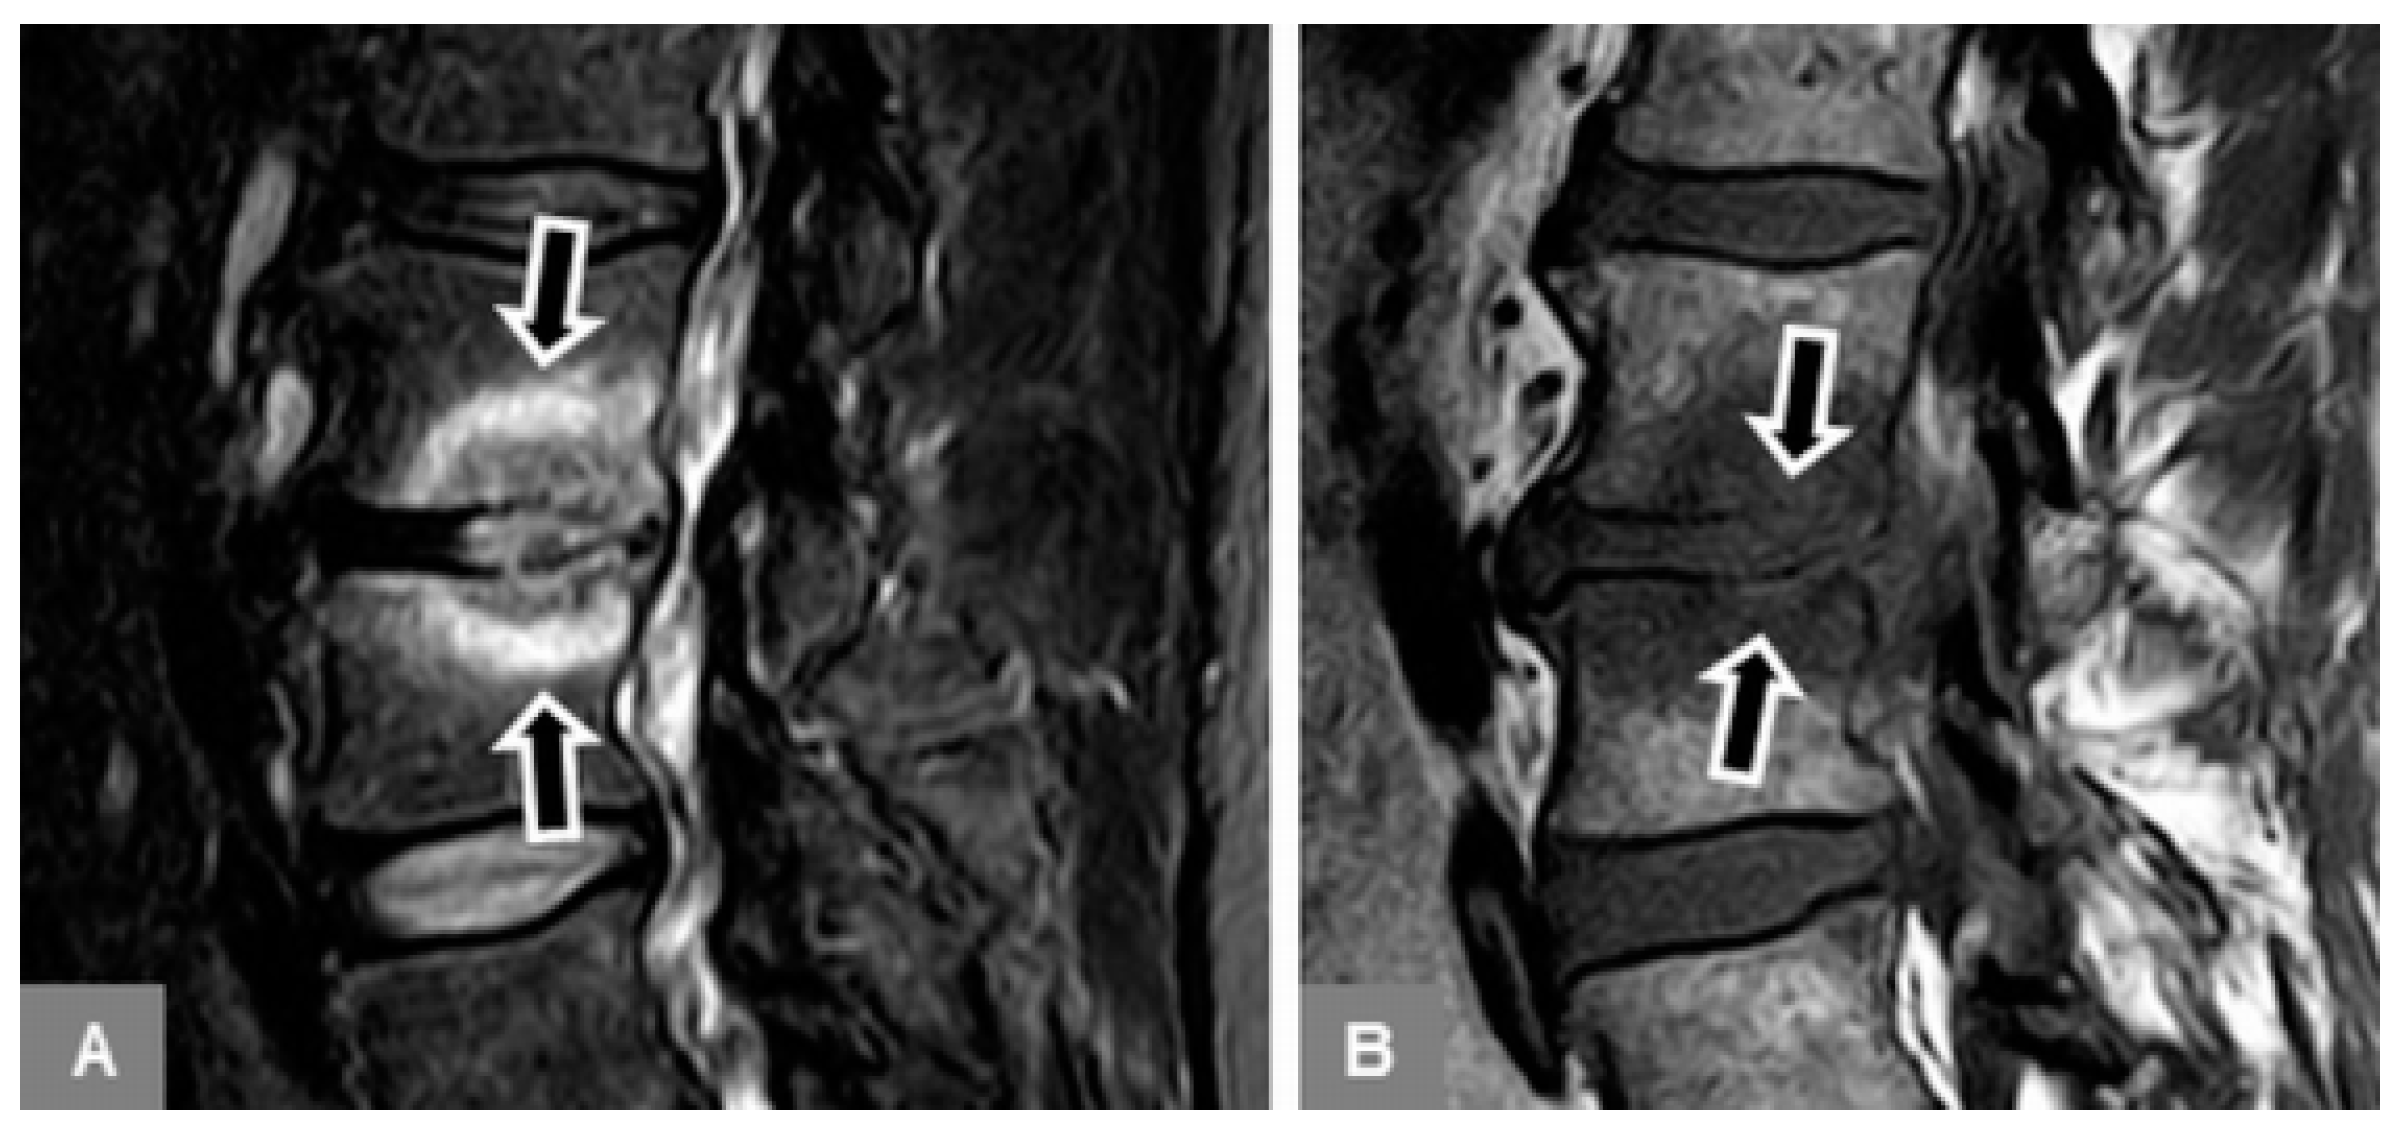

3.1. Bone Marrow Edema Extent, T1-w Signal Ratios of Edema to Unaffected Bone, and Visual T1-w Signal Assessment